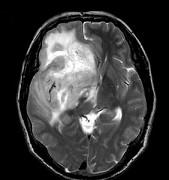

问题 男,55岁,头胀感1年余,头痛3日,请根据所提供图像,选择最可能的诊断()

选项 A.(右额颞)病毒性脑炎 B.(右额颞)星形细胞瘤 C.(右额颞)淋巴瘤 D.(右额颞)少突胶质细胞瘤 E.(右额颞)胶质母细胞瘤

答案 D